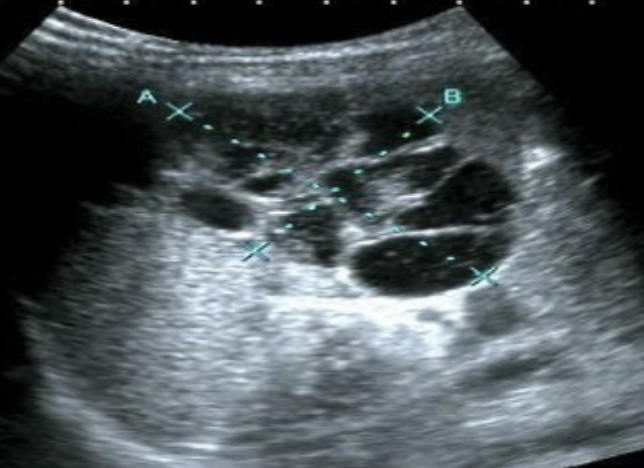

Pancreatic Pseudocyst → peripancreatic fluid collection from trauma or pancreatitis (4-6 week onset after pancreatitis)

clinical hx: trauma, hx of pancreatitis

s/sx: patient will feel better because of walled off inflammation, rupture → sudden shock and peritonitis, ascites if ruptures into abdomen

2D US: not always spherical, usually located in lesser sac (anterior to pancreas and posterior to stomach)

color doppler: avascular

DDX: true cyst